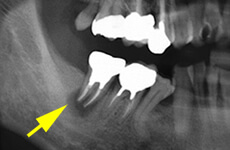

根の先の病気

主に虫歯が原因で、細菌が歯の中に通っている神経の管を通って神経自体に炎症を起こしたり、根の先に膿を作ることがあります。感染してしまった部分をきれいにとり、清掃をして、きれいになったところで細菌が増えないように薬をつめます。

- 歯根端切除術

歯の根の治療だけでは治癒に期待が持てない場合には、すぐに抜歯はせずに、歯肉をあけて根の先の膿を持った部位にアプローチする、歯根端切除術というものがあります。

当院では歯を残すことを前提にし、この歯根端切除術を採用していますが、これで治癒の見込みがない場合には再植→移植へと段階を追って治療法を決めております。状態が悪く残せないかもしれない歯を何とか残す方法のひとつでもあります。